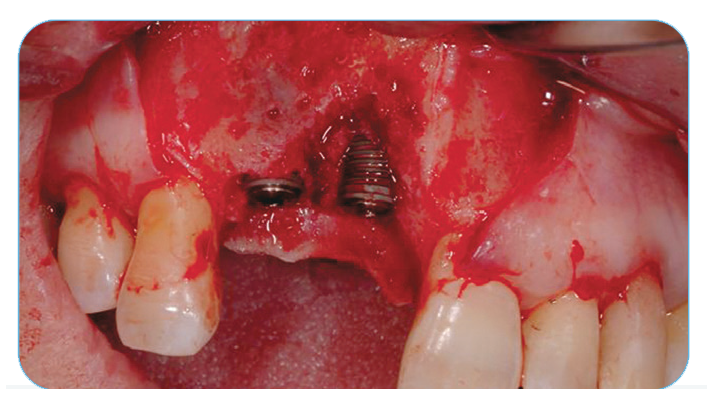

Anterior Ridge Augmentation

Fig. 5. Clinical appearance of the regenerated site at four months, after removing the remnants of the membrane.